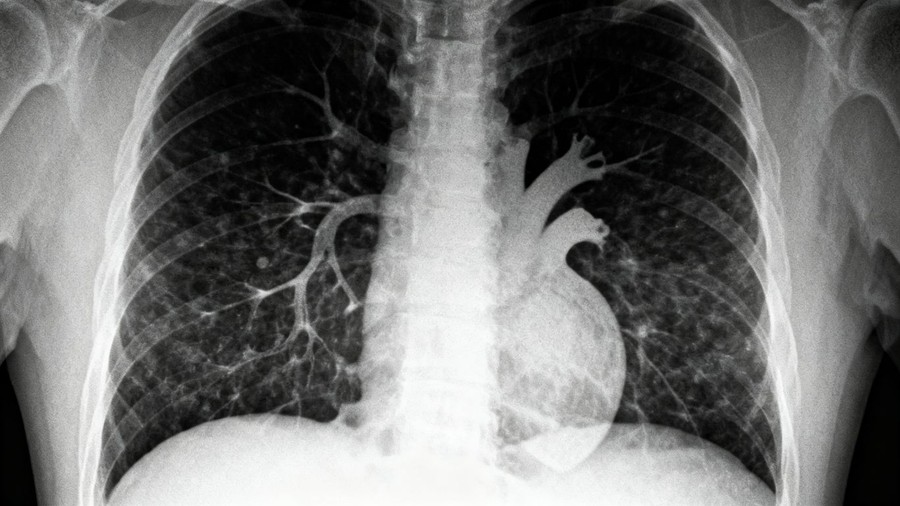

Figuring out if someone has asbestos-related lung cancer involves a few key steps. First, doctors will talk with you about your health history and any potential exposure to asbestos you might have had. This conversation is really important because knowing about past exposure can guide the diagnostic process. After that, imaging tests are usually done. These can include:

- Chest X-rays

To get a more definitive answer, doctors might perform procedures like a bronchoscopy or a biopsy. These allow them to take small tissue samples from the lungs. These samples are then looked at under a microscope to confirm the presence of cancer and determine its type. Sometimes, symptoms like shortness of breath or chest pain can be indicators of conditions like asbestosis, which is why a thorough evaluation is necessary.